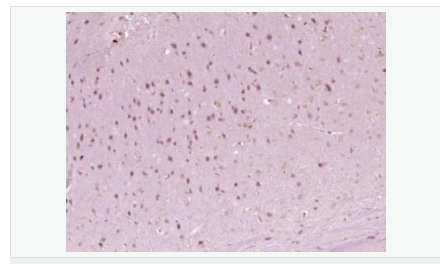

| 產(chǎn)品介紹 | The Hox homeobox genes encode proteins that are transcriptional regulators with an established role in embryonic development. HoxA6 (homeobox A6), also known as HOX1B, is a 233 amino acid protein that localizes to the nucleus. Expressed during embryonic development, HoxA6 functions as a sequence-specific DNA-binding transcription factor that is part of a regulatory mechanism that provides cells with positional identities during development. Via its ability to bind DNA, HoxA6 plays an important role in the regulation of gene expression, as well as morphogenesis and differentiation. The gene encoding HoxA6 maps to human chromosome 7, which houses over 1,000 genes and comprises nearly 5% of the human genome. Defects in some of the genes localized to chromosome 7 have been linked to Osteogenesis imperfecta, Williams-Beuren syndrome, Pendred syndrome, Lissencephaly, Citrullinemia and Shwachman-Diamond syndrome. Function: Sequence-specific transcription factor which is part of a developmental regulatory system that provides cells with specific positional identities on the anterior-posterior axis. Tissue Specificity: Nucleus. Similarity: Belongs to the Antp homeobox family. Contains 1 homeobox DNA-binding domain. SWISS: P31267 Gene ID: 3203 Database links: Entrez Gene: 3203 Human Entrez Gene: 15403 Mouse Omim: 142951 Human SwissProt: P31267 Human SwissProt: P09092 Mouse Unigene: 679517 Human Unigene: 222030 Mouse Important Note: This product as supplied is intended for research use only, not for use in human, therapeutic or diagnostic applications. |